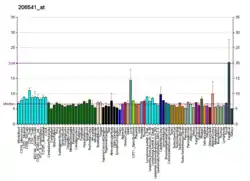

| |||||||||||||||||||||||||||||||||||||||||||||||||||

| |||||||||||||||||||||||||||||||||||||||||||||||||||

| |||||||||||||||||||||||||||||||||||||||||||||||||||

| |||||||||||||||||||||||||||||||||||||||||||||||||||

| |||||||||||||||||||||||||||||||||||||||||||||||||||

| |||||||||||||||||||||||||||||||||||||||||||||||||||

| |||||||||||||||||||||||||||||||||||||||||||||||||||